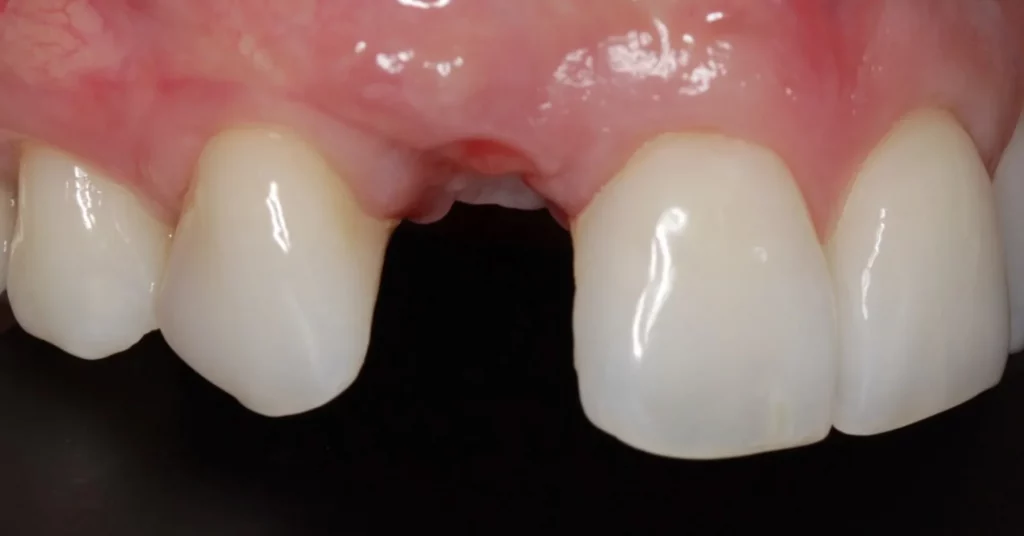

This lady was very upset after a dumbbell hit her mouth in the gym and knocked the front tooth out.

A temporary bridge was made to avoid her having to wear a temporary denture during the teatment, which is less comfortable.

A single implant with bone grafting was placed.

Once the implant was bedded into the bone, a new porcelain crown was fitted on the implant, and a new crown was placed on the adjacent tooth to match in better.